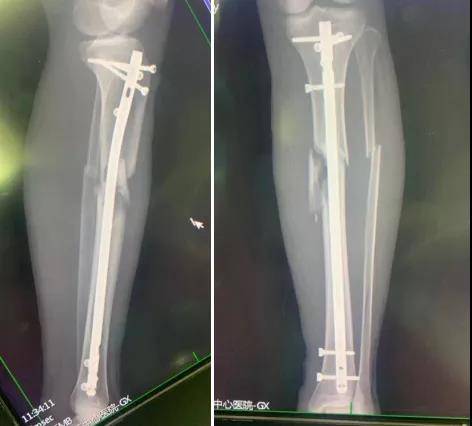

X光片显示 , 患者左胫骨近端粉碎性骨折 , 左腓骨骨折 。 因骨折情况严重 , 局部肿胀明显 , 该院骨科主任郭树章判断患者有出现“骨筋膜室综合征”的危险 。

待患者左小腿情况稳定后 , 由副主任医师李晓东带领主治医师冯凤辉、刘绍铭为患者手术 , 实施了这一手术方案 。 术中非常顺利 , 患者目前已回到病房 , 正在恢复中 。

髓内钉技术则是微创手术 , 通过几处1-3cm切口就能完成手术 , 很好地保护了骨膜等骨折周围软组织 , 十分有利于术后骨折愈合 。 该手术避免了传统手术中将膝关节极度屈曲才能置入髓内钉的缺点 , 在半伸直位就可以轻松完成手术 , 有利于术中透视 , 而且易于骨折复位及维持 , 操作简便 , 患者可以尽早开始功能锻炼 , 术后恢复较快 , 该术式值得推广使用 。